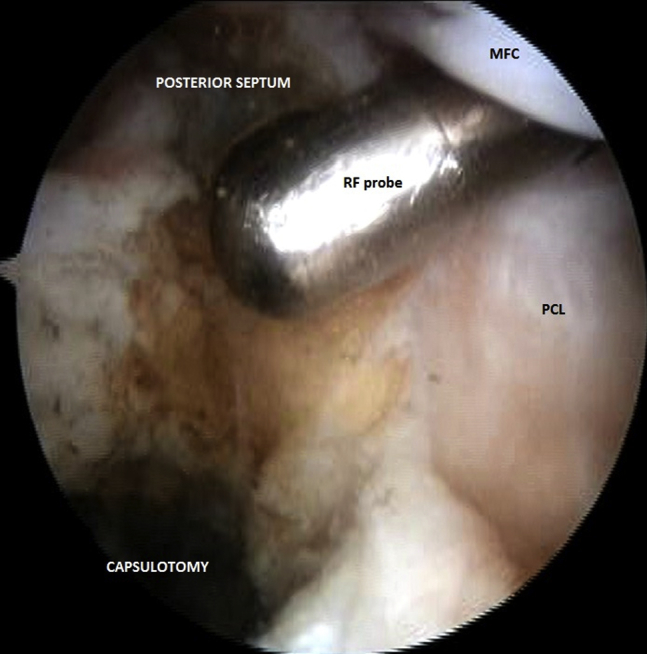

Fig 3.

Arthroscopic view from posteromedial portal in left knee joint. The radiofrequency (RF) probe, introduced through an additional anteromedial parapatellar portal, is used to extend the sectioning of the posteromedial capsule laterally and partially remove the posterior septum. (MFC, medial femoral condyle; PCL, posterior cruciate ligament.)